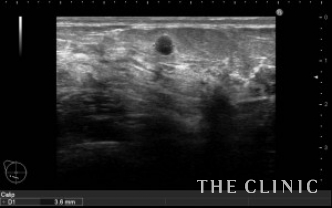

No.23でご紹介した方のオイルシストです。

エコー下にて穿刺吸引を行いました。

吸引後です。